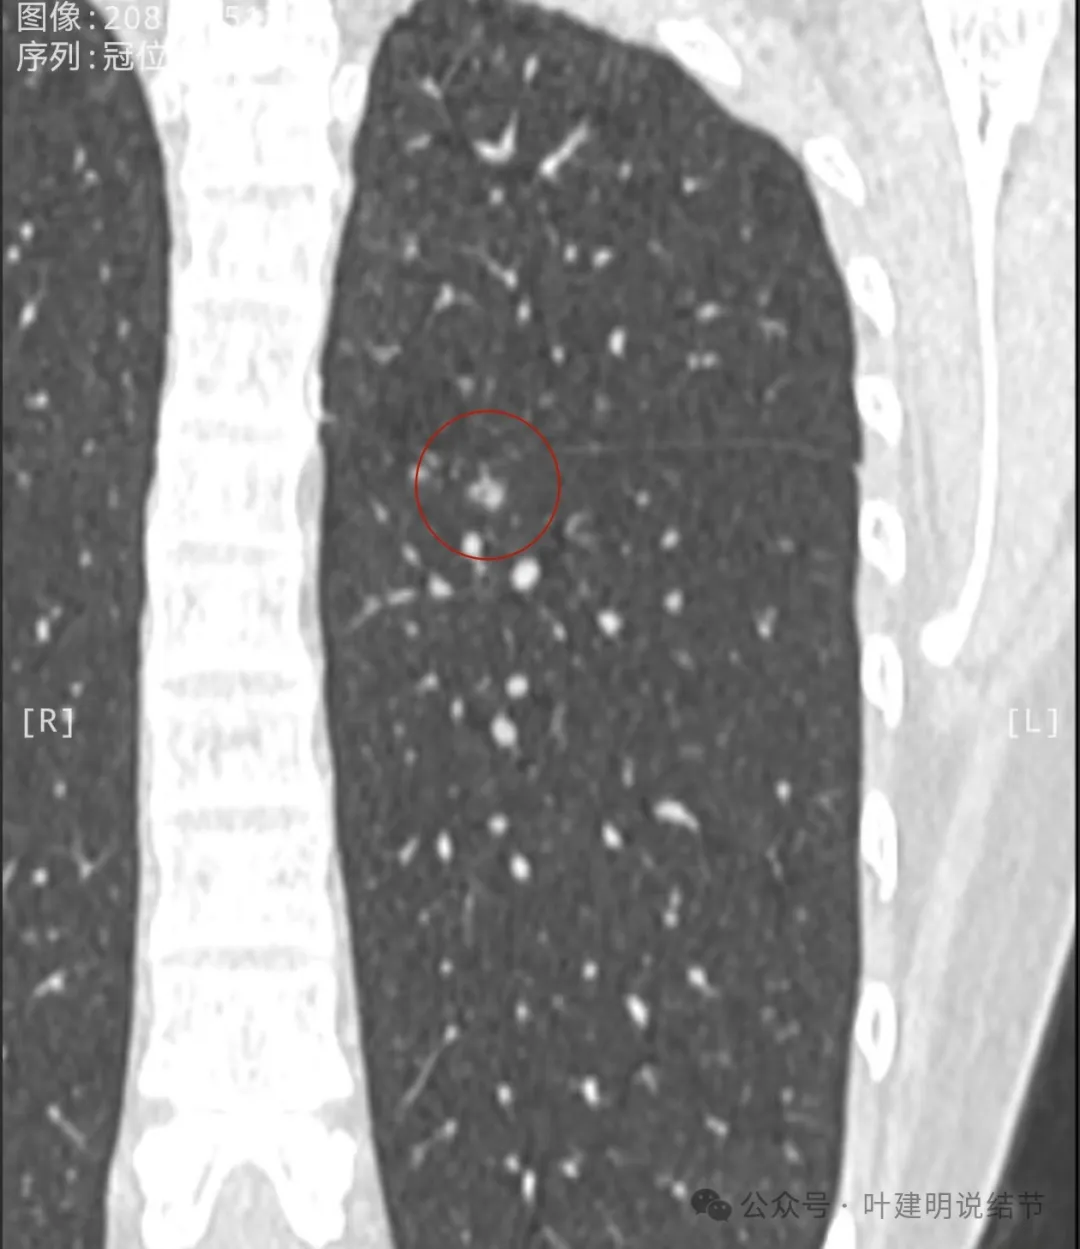

冠状位实性位小空泡征的样子,与叶间裂之间有小条状相连,整体轮廓较清,空泡壁厚薄不均。